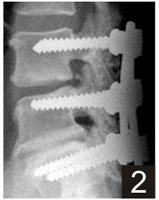

Porosity and Pore Size - The porosity of

60 to 70 percent with pore size ranging between

100-300 µm is the most optimum for bone in

growth.